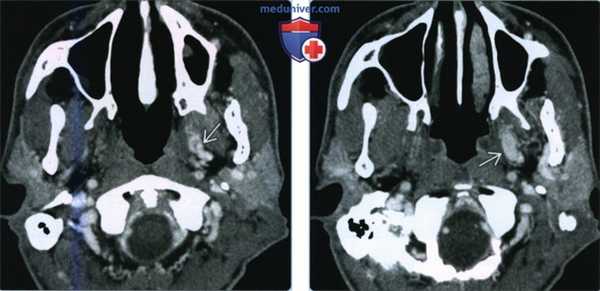

(Слева) При КТ с КУ в аксиальной проекции в медиальном жевательном и окологлоточном пространствах визуализируется участок накопления контраста волнообразной формы, который представляет собой увеличенное, асимметричное крыловидное венозное сплетение. Аномалия была обнаружена случайно. Обратите внимание, что плотность после введения контраста не отличается от плотности других вен.

(Справа) При КТ с КУ, на аксиальном срезе чуть выше предыдущего определяется увеличенное венозное сплетение, которое больше напоминает новообразование. И хотя подобная картина может насторожить врача в отношении периневральной опухолевой инвазии нижнечелюстного нерва, участок накопления контраста расположен иначе, чем предполагаемый ход ЧH V3.

2. КТ при ассиметрии крыловидного венозного сплетения:

• КТ без КУ:

о Без контраста визуализируется плохо

• КТ с КУ:

о Асимметричные волнообразные участки накопления контраста в жевательном и окологлоточном пространствах

• КТ-ангиография:

о КТ-ангиография/КТ-венография тонкими срезами, лучше всего визуализируется в венозную фазу

- Накопление контраста такое же, как и в других венах

(Справа) При КТ с КУ, на аксиальном срезе чуть выше предыдущего определяется увеличенное венозное сплетение, которое больше напоминает новообразование. И хотя подобная картина может насторожить врача в отношении периневральной опухолевой инвазии нижнечелюстного нерва, участок накопления контраста расположен иначе, чем предполагаемый ход ЧH V3. (Слева) При КТ с КУ в аксиальной проекции в медиальных отделах жевательного пространства наблюдается участок накопления контраста, напоминающий объемное образование. На самом деле он представляет собой асимметричное увеличенное крыловидное венозное сплетение.